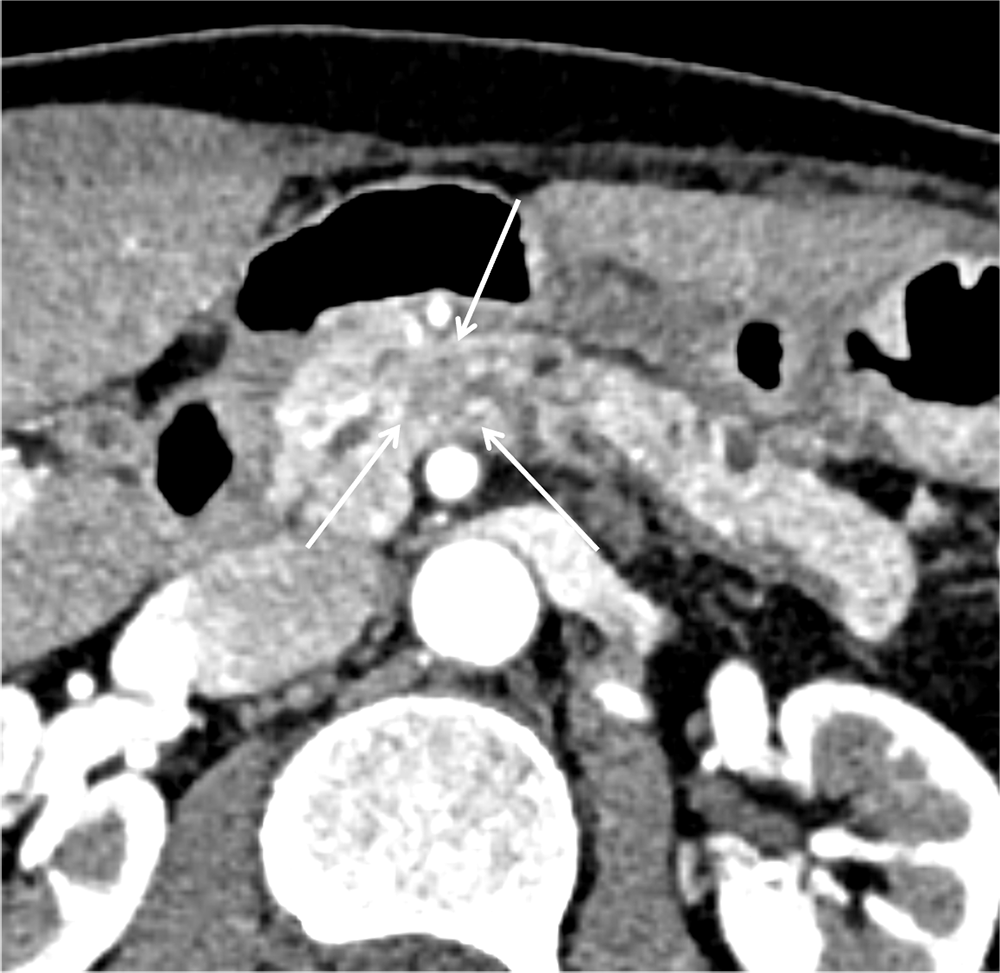

Dual energy CT を用いた膵dynamic CT検査にて膵頭部癌と診断。膵頭十二指腸切除術および門脈(上腸管膜静脈)合併切除再建術を施行され、浸潤性膵管癌、浸潤径約10mm(pT1b)、脈管浸潤なしと診断された。

本症例では、腫瘤形成以外に尾側の主膵管拡張を認めたため、単純CTでも病変の存在を指摘することは可能であったが、通常膵癌は単純CTでは正常膵実質と等吸収を呈するため、特に小径の膵癌の場合は随伴する主膵管拡張などの所見がはっきりしない場合もあり、指摘困難な場合がある。典型的な膵癌のDynamic CTでの造影パターンは、病変が最も明瞭となる膵実質相では周囲膵実質と比較して相対的に低吸収で、漸増性に造影され、遅延相では相対的に等~軽度高吸収を呈する。しかし、小径の膵癌(3cm以下)の場合は、膵実質相や門脈相で低吸収を呈さず、遅延相で高吸収として描出される傾向にあると言われており(2)、注意を要す。Dynamic CTは、正常膵実質と腫瘤部とのコントラストを得ることで病変の検出が容易となり、形状や造影パターンなどを評価することで他の膵病変と膵癌との鑑別にも有用である。また、局所進展度の評価にも有用で、膵癌の診断や治療方針決定に重要な役割を担う。

さらにthinスライスのCT画像、MPR(multi-planar reconstruction)、Dual-energy CTを用いた低エネルギーレベルの仮想単色X線画像やIodine mapの併用で、検出能向上や病期診断の精度向上につながると考えられる。Iodine mapは、Dual energy CTのデータからヨード造影剤を抽出して画像化したもので、ヨード濃度とその分布を把握することができる。本症例でも、Iodine mapでは病変と周囲膵実質のヨード濃度の差がわかりやすく、病変をより認識しやすくなった。また、MPR像を用いることで、通常の水平断面像と比べて、病変と主膵管との位置関係の把握が容易となった。